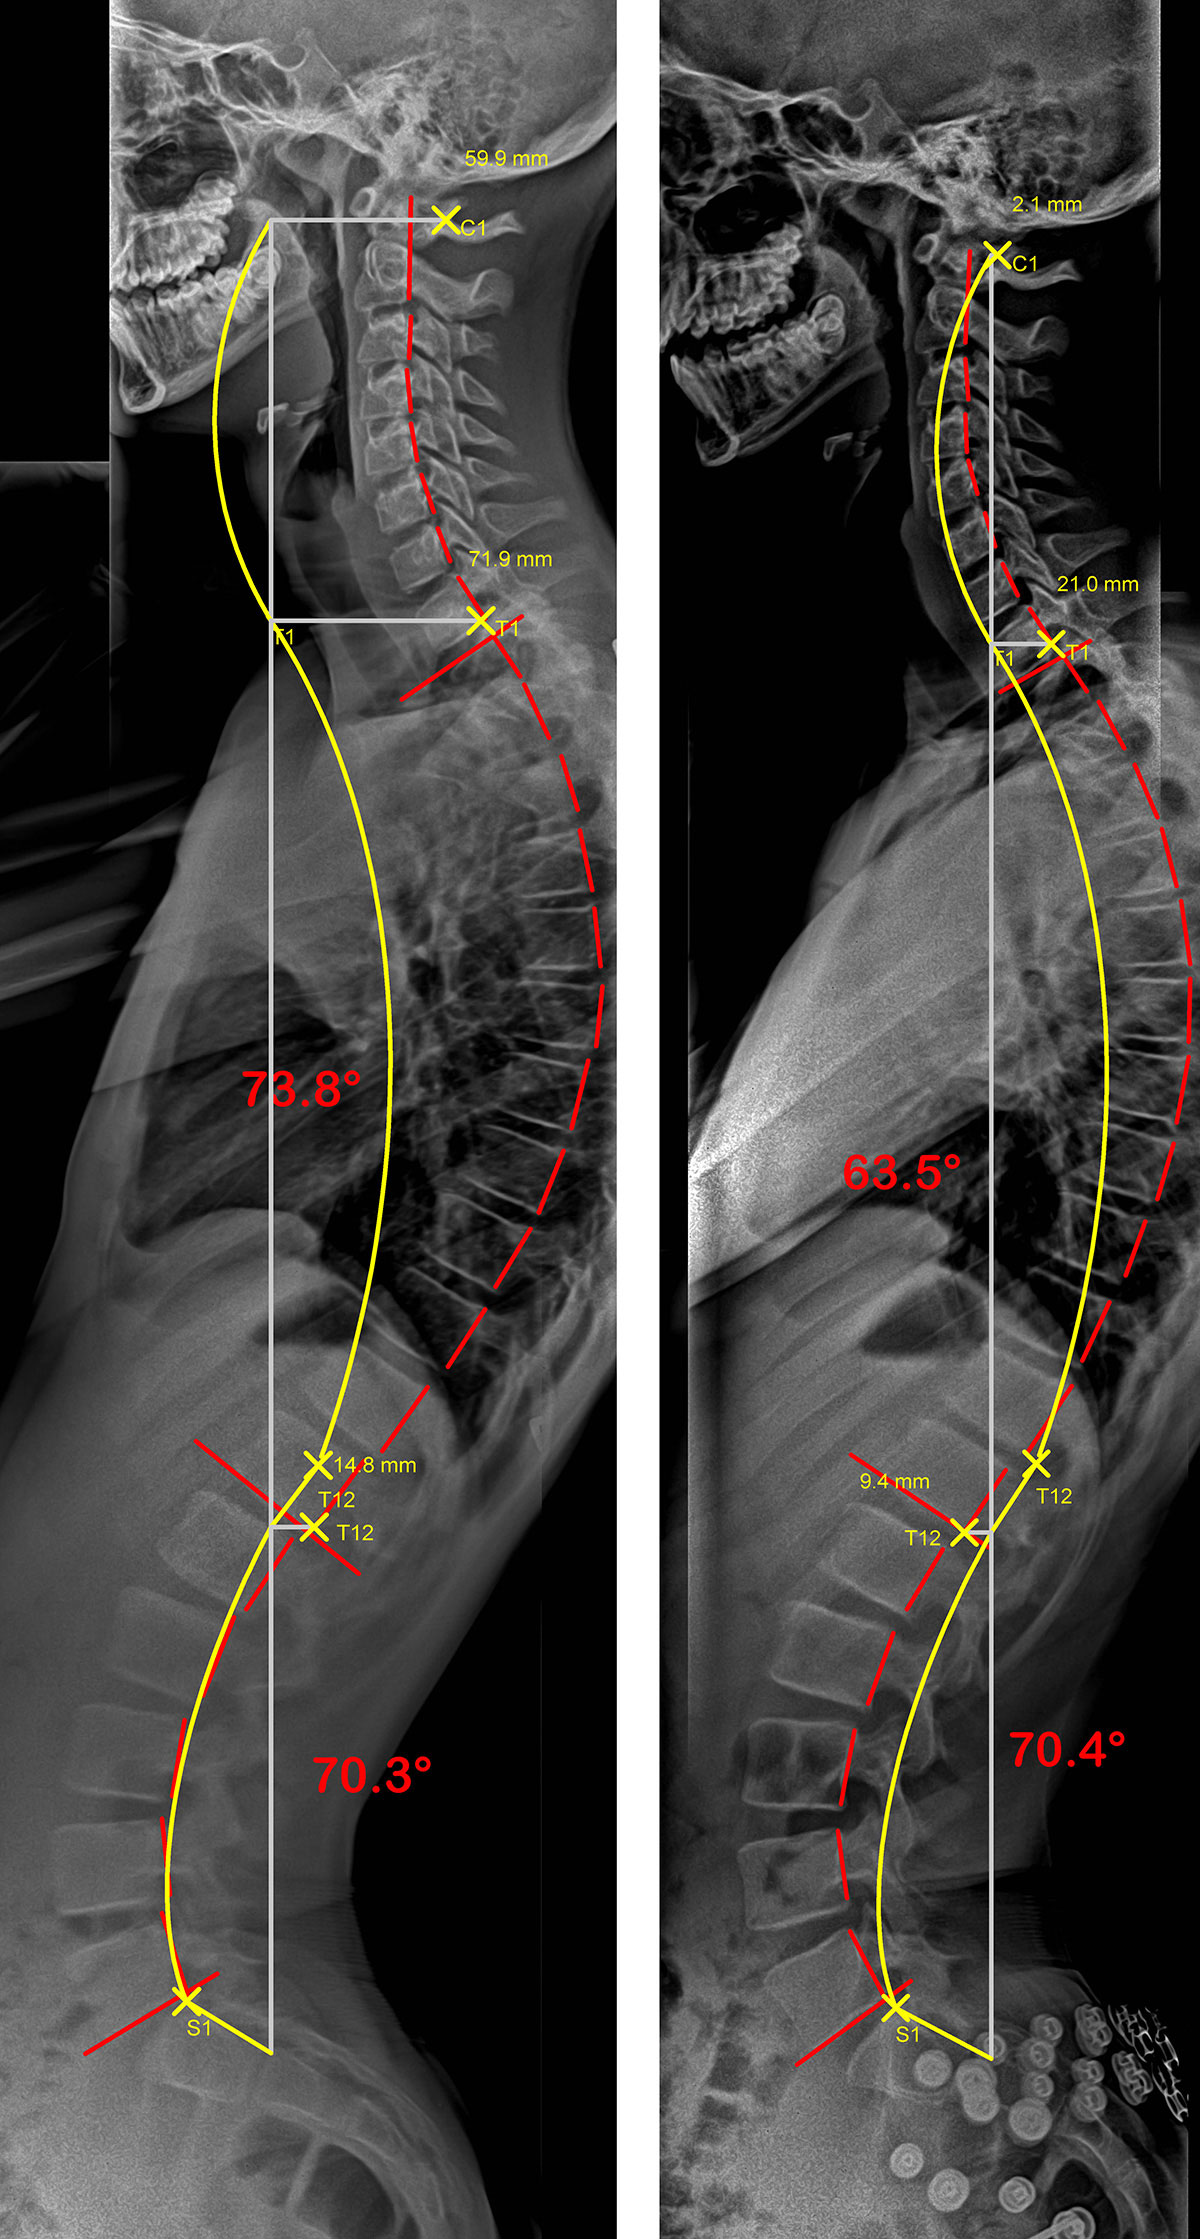

Le cas d’une adolescente avec une hypercyphose, sans et avec SpineCor®.

On remarque sur les radiographies que le simple fait de porter SpineCor® réduit la courbure de la colonne vertébrale d’environ 10° et améliore considérablement son alignement postural global car la ligne jaune représente l’idéal et la rouge le profil de la colonne vertébrale de la patiente.